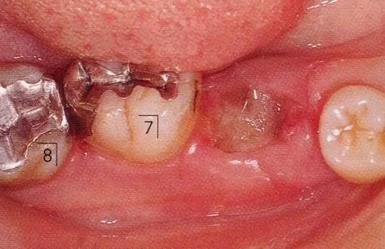

360截圖20170422101910161.jpg

▲圖7-1

對上頜前牙進行初期治療后的咬合面觀。右上2,3存在炎癥。